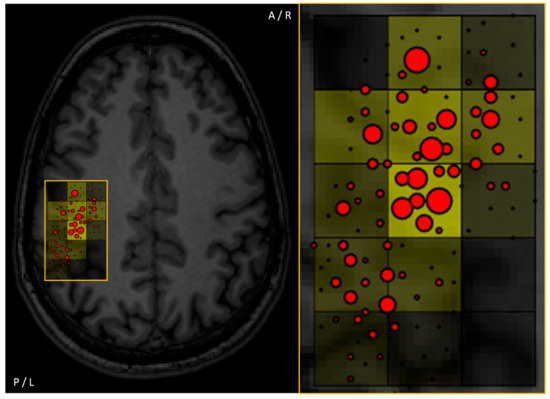

3.3. Stimulation Grid

- Julkunen, P. Methods for estimating cortical motor representation size and location in navigated transcranial magnetic stimulation. J. Neurosci. Methods 2014, 232, 125–133. [Google Scholar] [CrossRef]